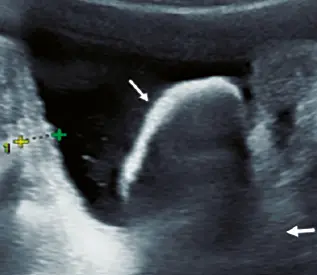

Fig: 11

Fig: 11, formación nodular ecogénica dentro de una imagen quística (flecha).